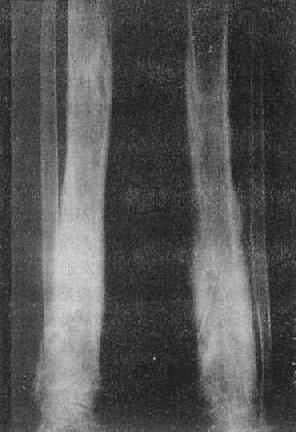

图2-1-12 胫骨慢性化脓性骨髓炎,花边状骨膜增生